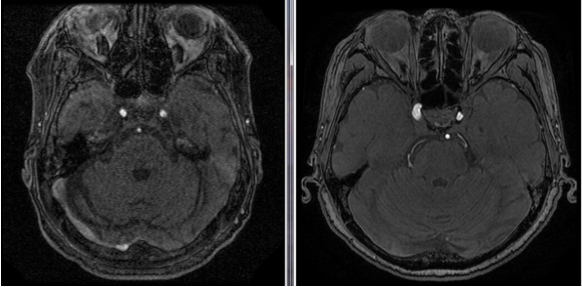

1.5T(左)与3.0T(右)的成像区别,你如何选择?

核磁共振成像